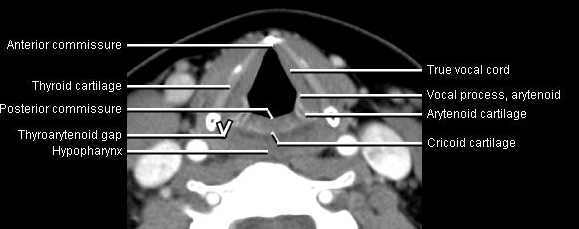

Phonation and dysphagia involve multiple coordinated structures in the larynx and pharynx. Radiation induced dysphagis appears to be related to dose to the phyaryngeal constrictor muscles and specific regions of the supraglottic and glottin larynyx.

Speech is impacted by doses to the epiglottis, base of tongue, aryepiglottic folds, false vocal cords upper esophageal sphincter and cricoid cartilage.

The mean laryngeal volume receiving > 50 Gy was a predictor of laryngeal edema. Vocal functions are usually well preserved with doses of 60 - 66 Gy. Dornfeld found a strong correlation between speech quality and dose to the ariepiglottic folds, pre-epiglottic space, false vocal cords and lateral pharyngeal walls at the level of the false vocal cords. A steep decrease in dose function was noted when doses exceeded 66 Gy.